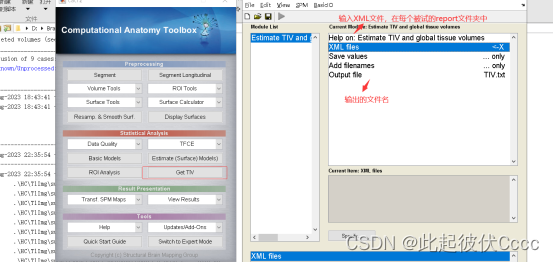

回到cat12操作主界面,在statistical analysis部分,点击Get TIV,如图所示:

输入文件后点击运行,在相应的默认文件夹下生成输出的.txt文件: